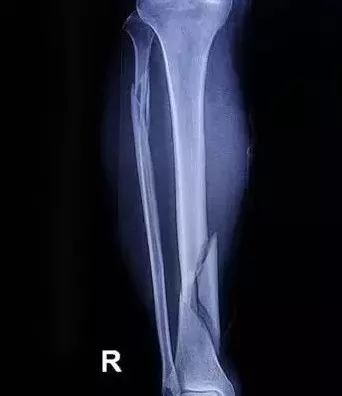

胫腓骨骨折 |

8-10周 |

局部血液供应:如果骨折部血液供应好,则骨折愈合快,如肱骨的外科颈(上端)骨折;反之,局部血液供应差者,骨折愈合慢,如股骨颈骨折。骨折类型也和血液供应有关,如螺旋形或斜形骨折,由于骨折部分与周围组织接触面大,因而有较大的毛细血管分布区域供应血液,愈合较横形骨折快。

骨折断端的状态:骨折断端对位不好或断端之间有软组织嵌塞等都会使愈合延缓甚至不能接合。此外,如果骨组织损伤过重(如粉碎性骨折),尤其骨膜破坏过多时,则骨的再生也较困难。骨折局部如出血过多,血肿巨大,不但影响断面的接触,且血肿机化时间的延长也影响骨折愈合。